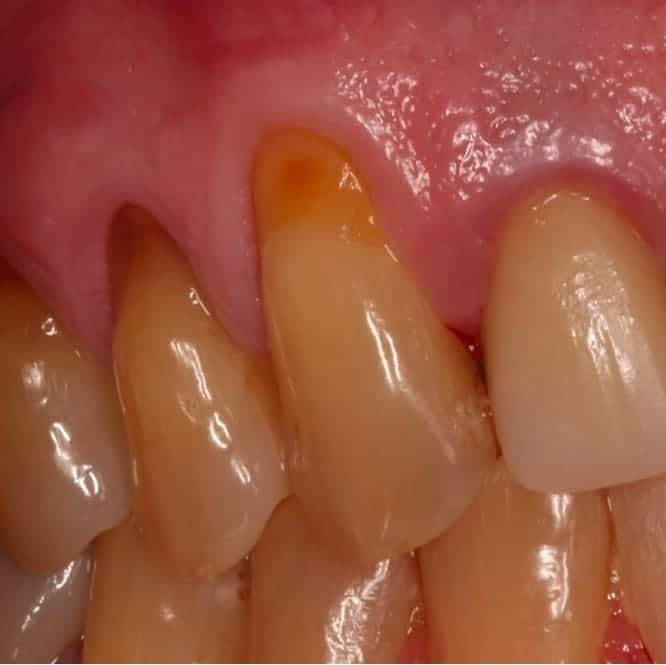

Before treatment showing severe gum recession with exposed and demineralized root surfaces on multiple teeth Before

Niko had watched his gums recede gradually over almost a decade. What began as mild sensitivity to cold had progressed to visible root exposure, discoloration, and constant discomfort across several teeth on his upper left side.

By the time he sought treatment, the roots weren't just exposed — they had become demineralized from years of unprotected contact with the oral environment. His general dentist referred him for a microsurgical root coverage consultation after determining the case was beyond standard treatment approaches.

Niko presented with Miller Class II and Class III recession affecting the upper left premolars and canine, with recession depths ranging from 4 to 6 millimeters. The exposed root surfaces were discolored, rough to probing, and showed visible signs of surface demineralization.

The surrounding tissue was thin and fragile — a biotype that predisposes patients to progressive recession without intervention. A high frenal attachment was also identified, placing additional tension on the marginal tissue.

Niko had avoided chewing on the affected side entirely. The thermal sensitivity was consistent and significant, and the exposed roots had become a source of daily discomfort.